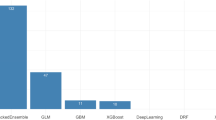

In the five ML models established using preoperative clinical data, the top commonly selected factors such as non-PDAC etiology, small pancreatic duct size, low glucose level, high hemoglobin, and high VATI for POPF occurrence (Fig. 2). Preoperative CT-based four DL models were developed, and gradient-guided class attention maps showed the areas that the models focused on (Fig. 3). The finally selected model was the soft voting-based ensemble model composed of two ML models (ANN and logistic regression) and one DL model (Inception Net). AUCs of the ensemble model in the training, validation, and test datasets were 0.969, 0.779, and 0.750, respectively. Sensitivity, and specificity were described in Supplementary Table 7. The Roberts model was not included in the ensemble model. The predictive performance of the ensemble model was enhanced as compared to individual ML and DL models.

In the preoperative CR-POPF model, ML models frequently selected non-PDAC etiology, high VATI, absence of diabetes, and smaller pancreatic duct size as important factors predicting CR-POPF. The selected hard voting-based ensemble model comprised three ML models (ANN, TabNet, and random forest) and two DL models (ResNet and ResNeXt); the Roberts model was not included. AUCs of Ensemble model in the training, validation, and test datasets were 0.936, 0.915, and 0.682, respectively, and the ensemble model showed better predictive performance than individual ML and DL models (Table 2).

Model development for POPF prediction

A schematic representation of the developed models is provided in Fig. 1, and details of model development are provided in Supplementary Method. Using the training dataset, we developed models for predicting POPF and CR-POPF using preoperative data. We developed five ML models (artificial neural network [ANN], tabular network, logistic regression, random forest, and gradient boosting) utilizing the clinical information and body composition data. To train the DL models, the training dataset was divided into the training and validation subsets, and four DL models (ResNet, DenseNet, ResNeXt, and Inception net) were created utilizing preoperative CT data. Ensemble voting was used to combine the developed ML models, DL models, and the prior models (Roberts model7) with soft or hard voting, and the model with the highest accuracy in the validation subset was chosen. Finally, the single preoperative comprehensive model was selected, and the predictive performance was evaluated using the separate test dataset. The codes used in this work are available in the GitHub repository (https://github.com/nolife119/POPF_ensemble).